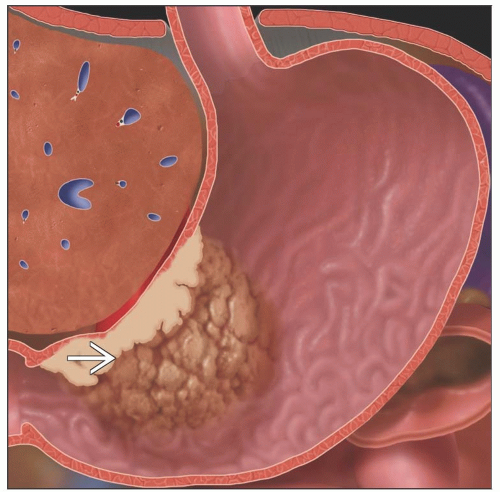

Carcinoma of the Gastric Antrum – Stomach Case Studies – CTisus CT Scanning

Ulcerating Gastric Cancer – Stomach Case Studies – CTisus CT Scanning

Imaging Findings of Gastric Carcinoma | IntechOpen